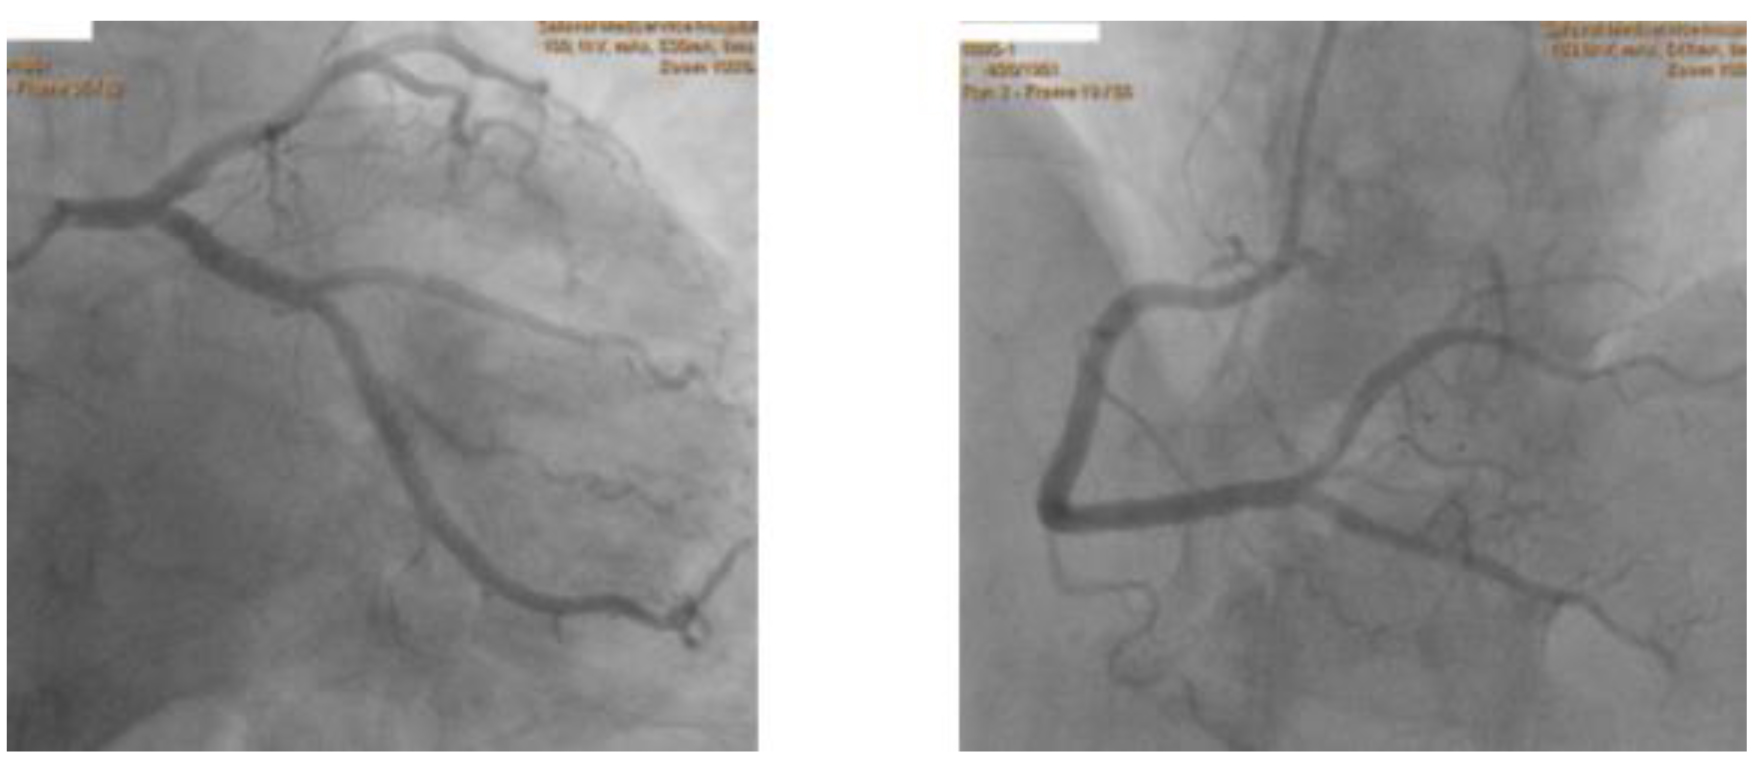

Так выглядят коронарные артерии при коронарографии (пример без патологии):